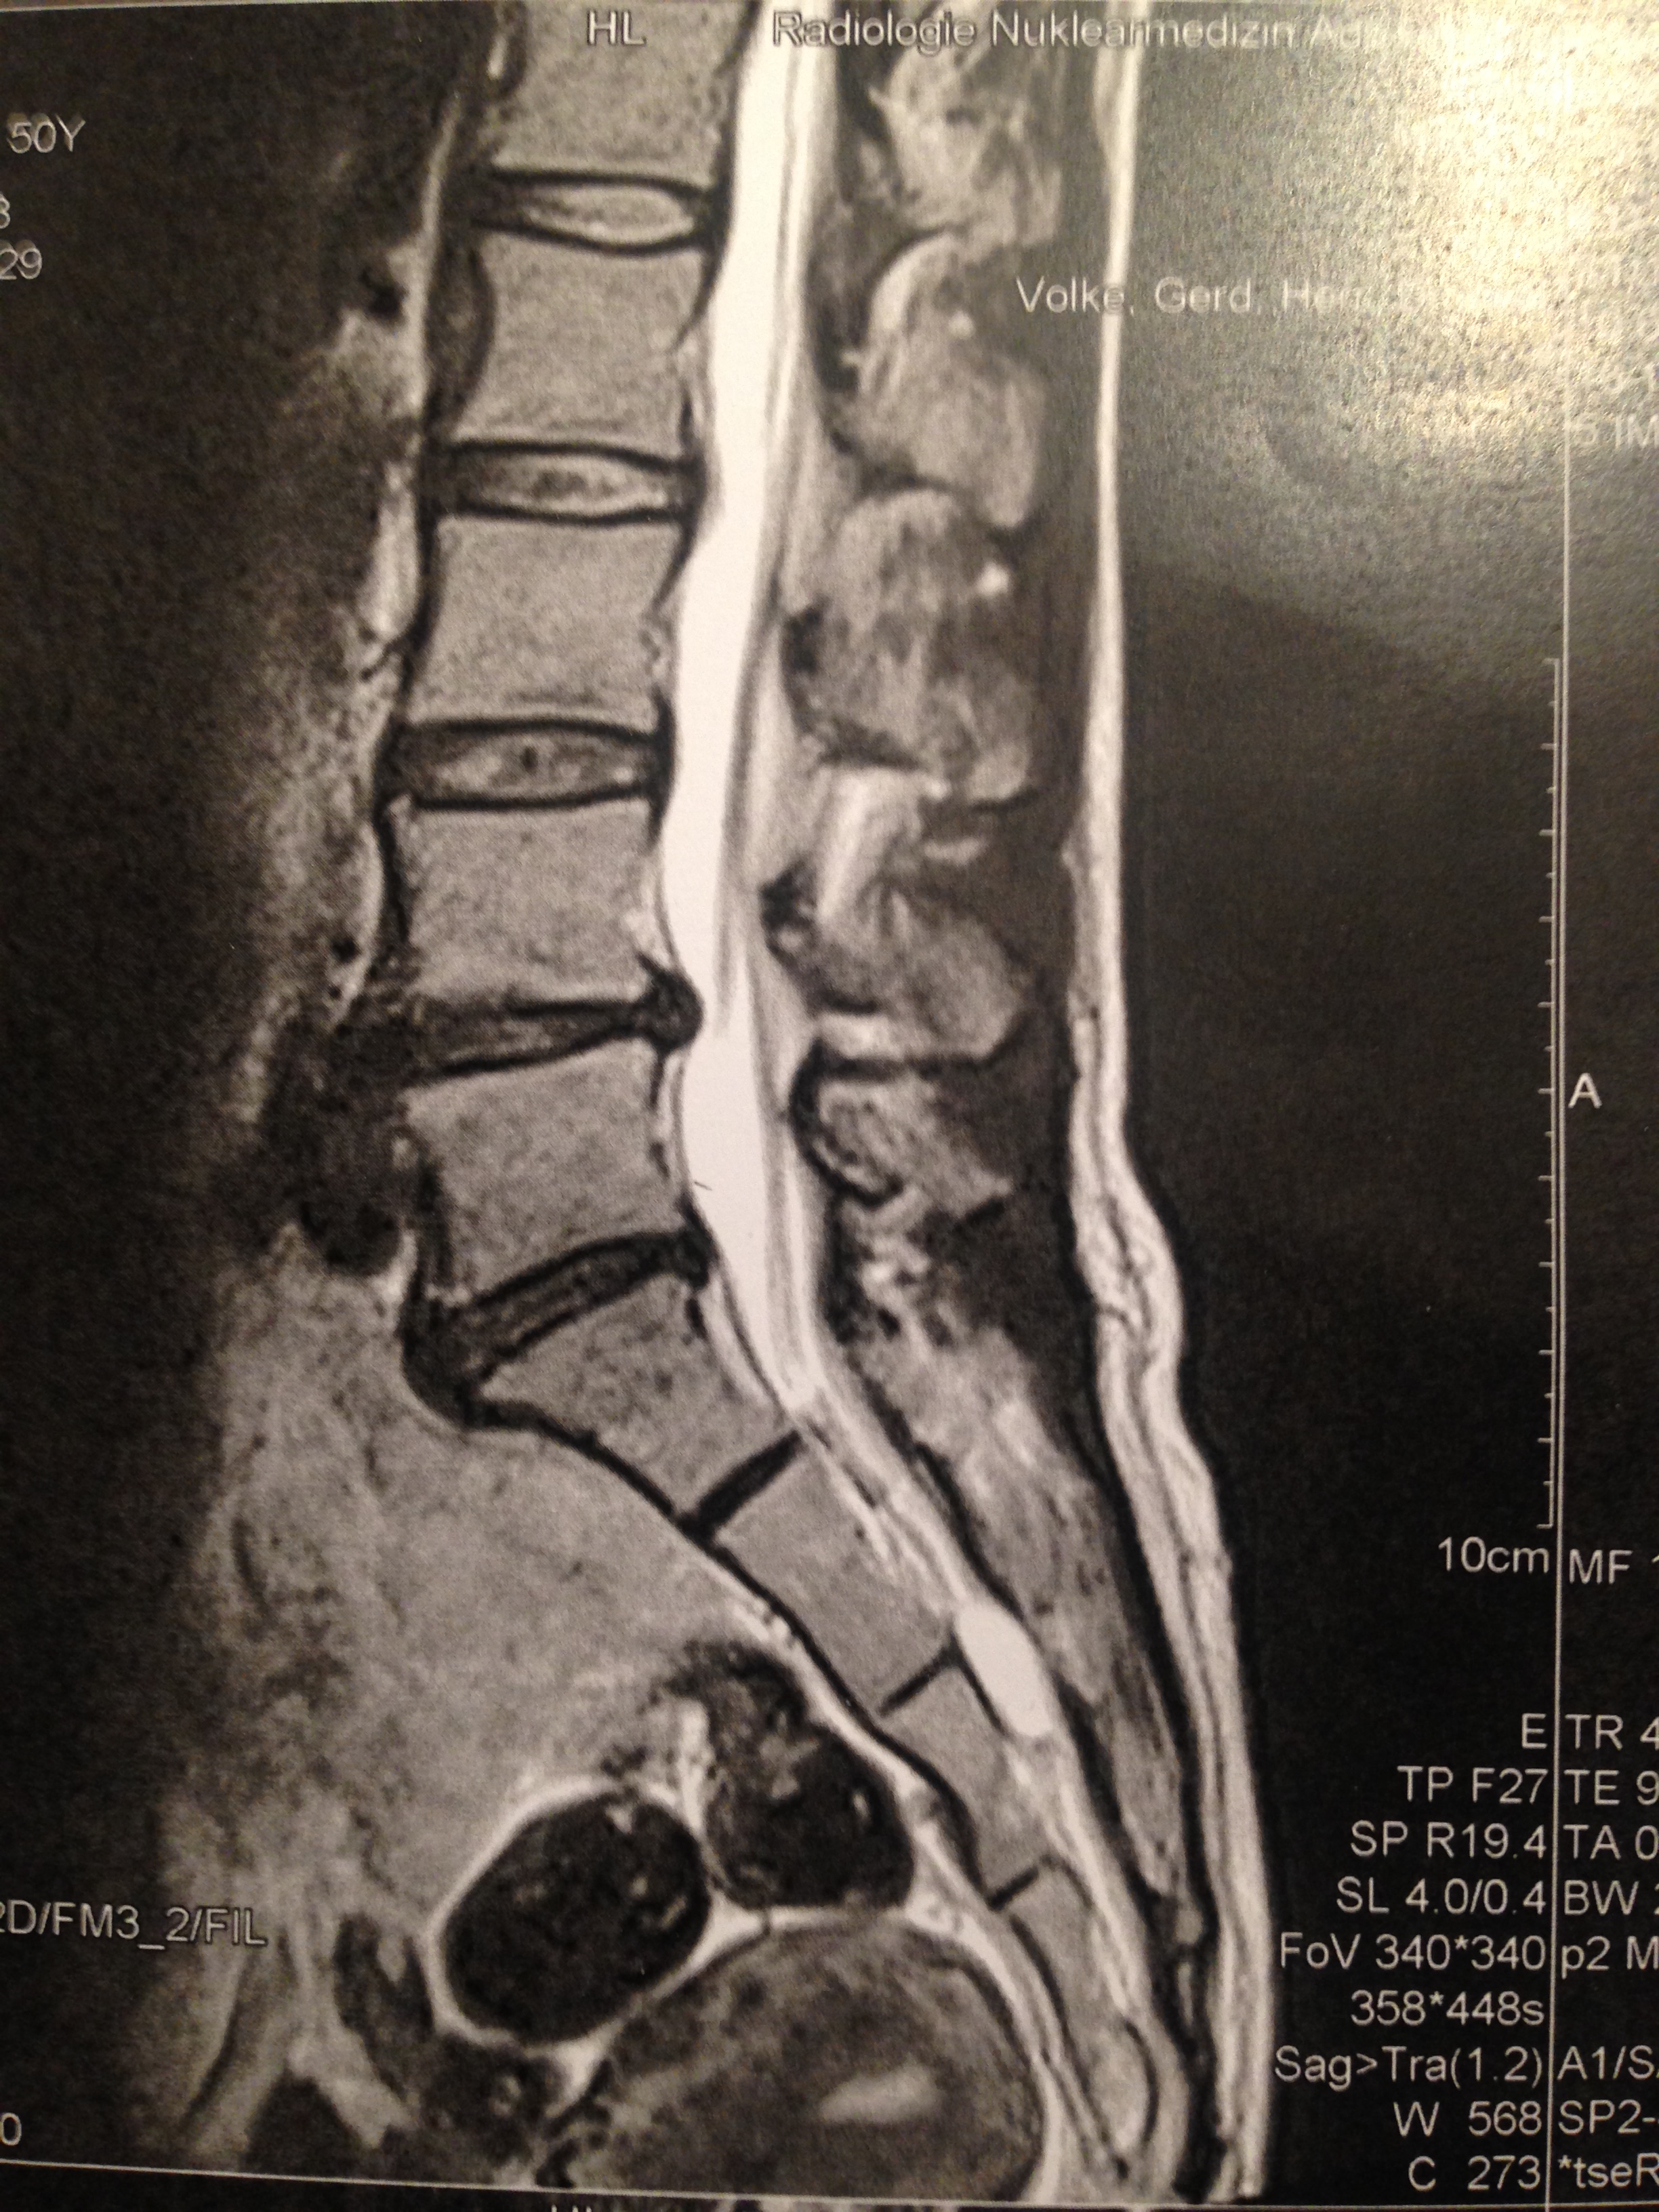

椎間盤突出,L4,L5的兩粒可愛小黃豆。

真的,生兩個孩子我也沒叫痛,怎麼腰間這兩粒如黃豆般大小的突出之物,可以把你的生活完完全全的扒下來。

(疼痛最嚴重時的感受,現已舒緩。希望同樣患有坐骨神經痛的朋友們都要有信心,疼痛會過去的,當然要接受適當的治療,治療路漫長,要堅持下去。)